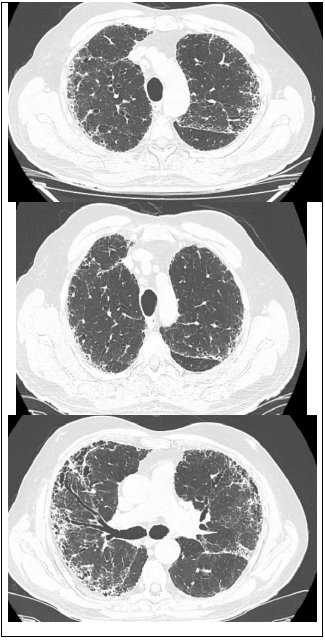

Leia o caso a seguir para responder às questões de 22 a 24.

Paciente 68 anos de idade, do sexo masculino, refere dispneia progressiva há 2 anos, inicialmente aos grandes esforços e atualmente aos pequenos esforços, associado com tosse seca frequente. Nega outros sintomas associados.

Ex-tabagista de 10 maços-ano, cessou o hábito há 20 anos.

Criou 2 pássaros em gaiola, em casa por 2 anos, cessou há 15 anos.

Trabalha em escritório de advocacia por toda a vida. Nega contato com mofo. Nega uso de medicações contínuas prévias ou atuais.

Ao exame em bom estado geral, leve dispneia, baqueteamento digital, IMC: 20, FR: 24irm, FC: 90 bpm, PA: 120x80mmHg, spO2 90% em ar ambiente. Ausculta pulmonar: estertores finos em velcro bibasais. Sem outras alterações.

Traz resultado de exame:

FAN negativo, FATOR REUMATÓIDE negativo

Espirometria: distúrbio ventilatório restrivo acentuado.

Tomografia de tórax: padrão típico de PIU (pneumopatia intersticial usual).

Qual é o tratamento indicado para esse paciente?

Leia o caso a seguir para responder às questões de 22 a 24.

Paciente 68 anos de idade, do sexo masculino, refere dispneia progressiva há 2 anos, inicialmente aos grandes esforços e atualmente aos pequenos esforços, associado com tosse seca frequente. Nega outros sintomas associados.

Ex-tabagista de 10 maços-ano, cessou o hábito há 20 anos.

Criou 2 pássaros em gaiola, em casa por 2 anos, cessou há 15 anos.

Trabalha em escritório de advocacia por toda a vida. Nega contato com mofo. Nega uso de medicações contínuas prévias ou atuais.

Ao exame em bom estado geral, leve dispneia, baqueteamento digital, IMC: 20, FR: 24irm, FC: 90 bpm, PA: 120x80mmHg, spO2 90% em ar ambiente. Ausculta pulmonar: estertores finos em velcro bibasais. Sem outras alterações.

Traz resultado de exame:

FAN negativo, FATOR REUMATÓIDE negativo

Espirometria: distúrbio ventilatório restrivo acentuado.

Tomografia de tórax: padrão típico de PIU (pneumopatia intersticial usual).

Qual é a melhor conduta para confirmar o diagnóstico desse paciente?

Leia o caso a seguir para responder às questões de 22 a 24.

Paciente 68 anos de idade, do sexo masculino, refere dispneia progressiva há 2 anos, inicialmente aos grandes esforços e atualmente aos pequenos esforços, associado com tosse seca frequente. Nega outros sintomas associados.

Ex-tabagista de 10 maços-ano, cessou o hábito há 20 anos.

Criou 2 pássaros em gaiola, em casa por 2 anos, cessou há 15 anos.

Trabalha em escritório de advocacia por toda a vida. Nega contato com mofo. Nega uso de medicações contínuas prévias ou atuais.

Ao exame em bom estado geral, leve dispneia, baqueteamento digital, IMC: 20, FR: 24irm, FC: 90 bpm, PA: 120x80mmHg, spO2 90% em ar ambiente. Ausculta pulmonar: estertores finos em velcro bibasais. Sem outras alterações.

Traz resultado de exame:

FAN negativo, FATOR REUMATÓIDE negativo

Espirometria: distúrbio ventilatório restrivo acentuado.

Tomografia de tórax: padrão típico de PIU (pneumopatia intersticial usual).

Qual é o diagnóstico mais provável para o paciente?